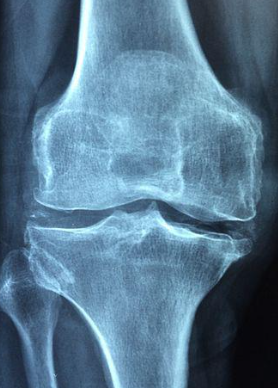

1) 관절 건강 개선 효능

NAG는 관절과 연골을 구성하는 성분으로 연골이 마모되거나 파열되지 않도록 도움을 줍니다. 또한 체내 히알루론산의 생성을 촉진해 관절을 싸고 있는 활액막을 생성하는데 도움이 됩니다.

2014년 한국 식품 저널에 따르면 NAG 섭취 후 16주 동안 관절염 통증 지표인 워맥 검사 결과 통증, 뻣뻣한, 신체기능 등이 점차 개선되었다고 보고되었습니다.

또한 NAG 적외선 체온 검사에서 무릎 통증이 조금씩 개선되는 효능이 있음을 확인했습니다. 20명의 관절염 초기 환자에게 NAG를 16주간 하루 1g씩 섭취하게 한 결과 만성 염증과 통증이 줄어들어 골관절염이 완화되었다고 보고했습니다.

2003년 신약과 임상에서도 8주 동안 NAG를 하루 1g씩 섭취하게 했더니 퇴행성 관절염이 개선되는 변화가 나타났다고 합니다.